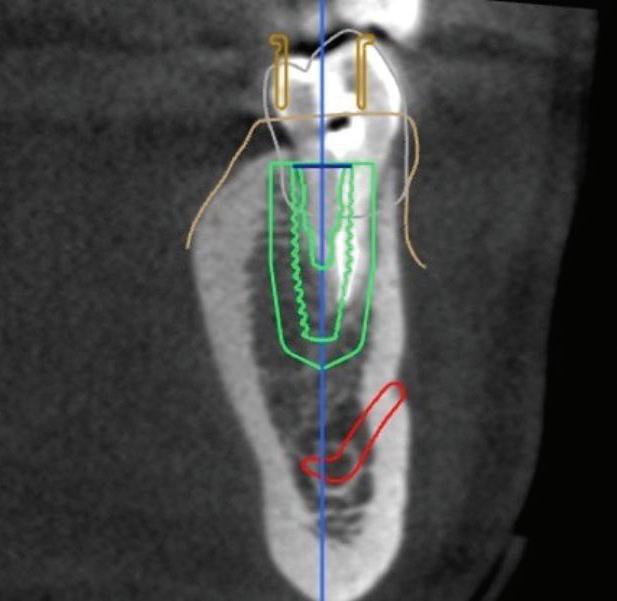

Figure 1: Radiographic Image of implants do not demonstrate bone loss due to the bisecting angle of the radiograph taken.

Figure 2: Radiographic image in a paralleling technique of implants dem onstrate moderate peri-implantitis with bone loss that will necessitate treatment.